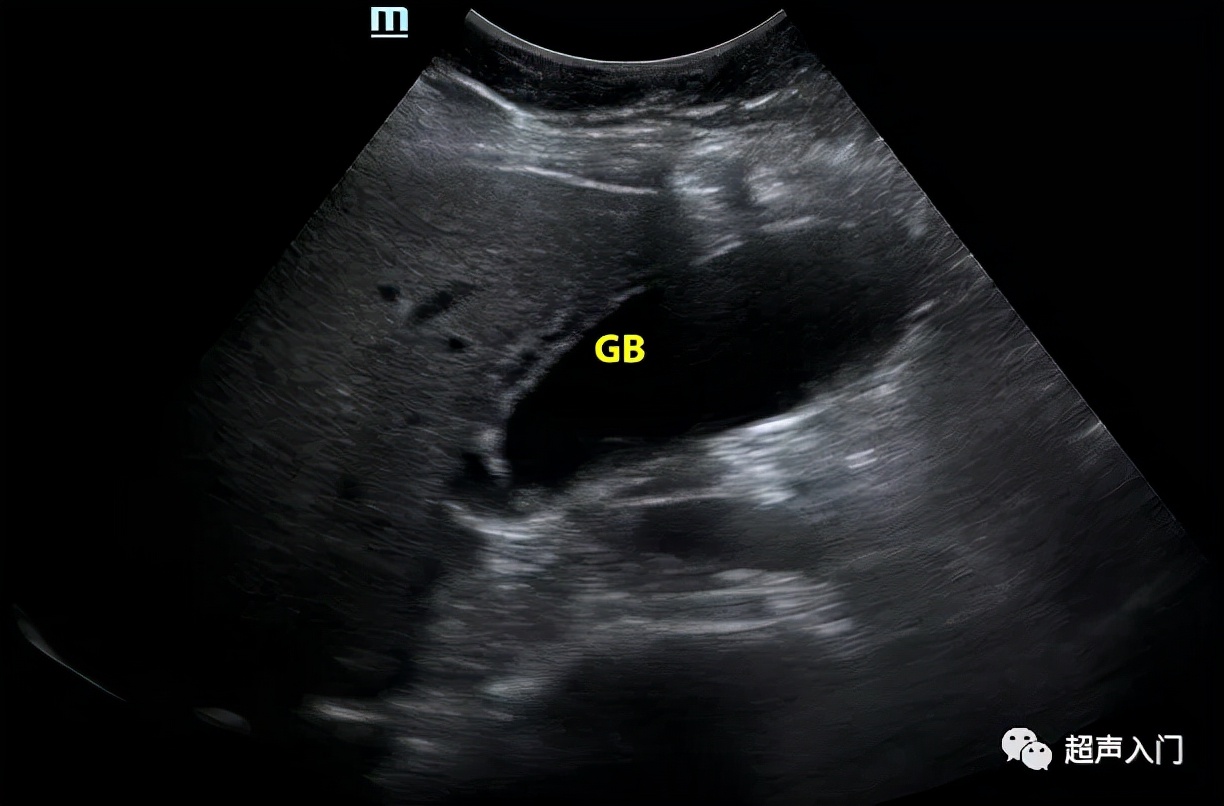

但常规超声往往很难对其进行准确分类,囊内透声好并不代表没有化脓,如上图,囊内透声很好,但患者持续发热,胆囊置管后,抽出脓性胆汁。

单纯性胆囊炎初期超声显示胆囊稍大囊壁轻度增厚,缺乏诊断特征。形成化脓性胆囊炎后声像图特征较明显,主要表现如下:

1、胆囊肿大常呈圆形或椭圆形,胆囊壁伸展呈饱满状,是胆囊张力增高所致,胆囊壁轮廓线模糊,外壁线不规则。

2、胆囊壁弥漫增厚,呈高回声,其间出现间断或连续的弱回声带,形成胆囊壁的“双边影”(double- laverecho)。

此征系浆膜下水肿、出血和炎性细胞浸润等改变所致。

3、胆囊切面无回声区内出现稀疏或密集的分布不均的细小或粗大回声斑点,呈云雾状,为胆囊积脓的表现。